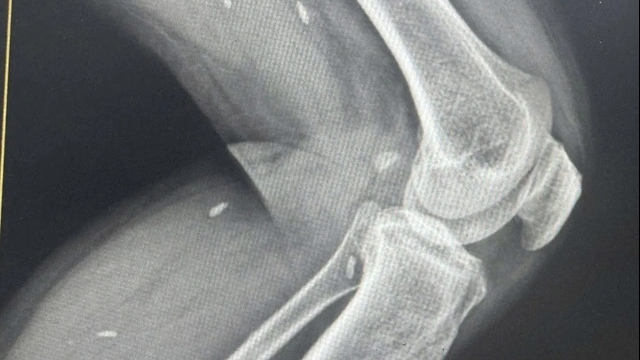

Bệnh nhân này sau đó được xác định đã tử vong ngoại viện. Bệnh viện cũng xác định nạn nhân tử vong có thể do bị nhồi máu cơ tim.